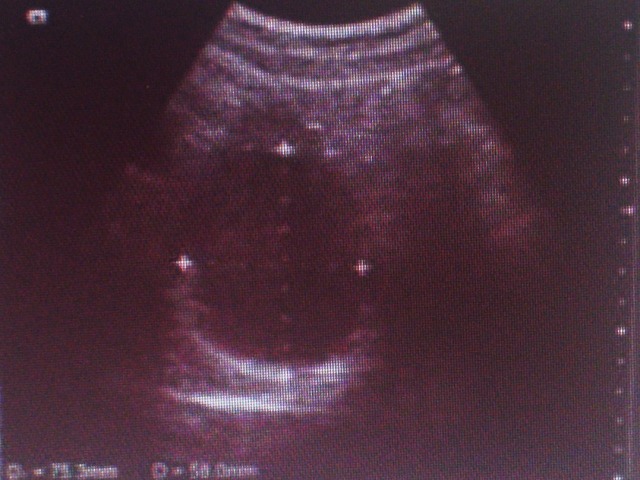

なんてことを思いながら、一緒にエコー画像を見ました。

(↑画像荒くてすいません。)

先生:「(まんまるな黒い物体を映して)これだね~。結構大きいよ。(機械を操作して大きさを図ってる)」

私:「ホントですね。」

先生:「押されて痛みはある?」

私:「うーん、圧迫されてる感はありますが、痛くないです。」